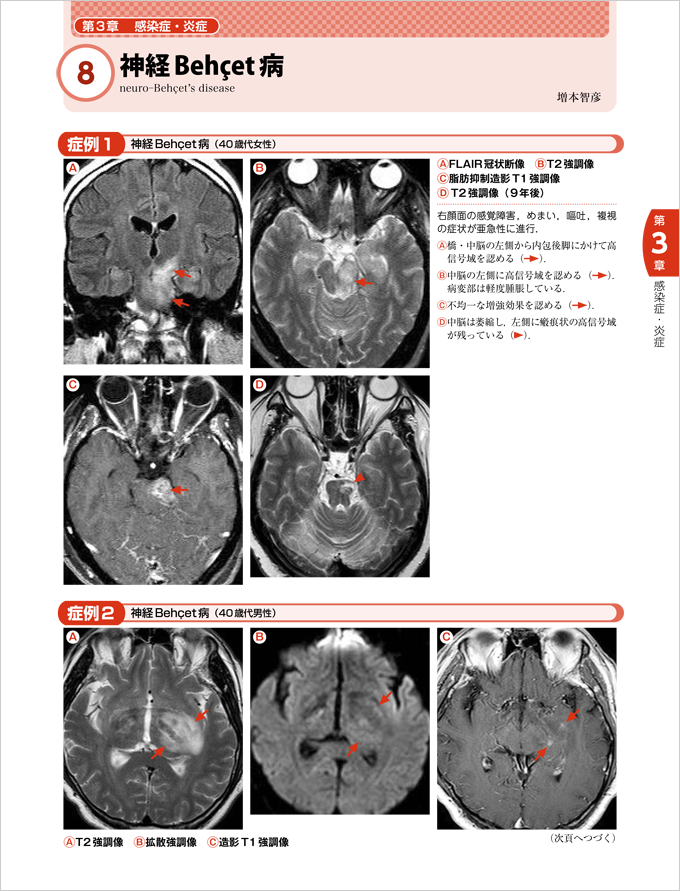

ネットオフ 送料得店 徹頭徹尾―疾患を見極め的確に診断する 頭部画像解剖 | 金博 蓮尾 医学一般